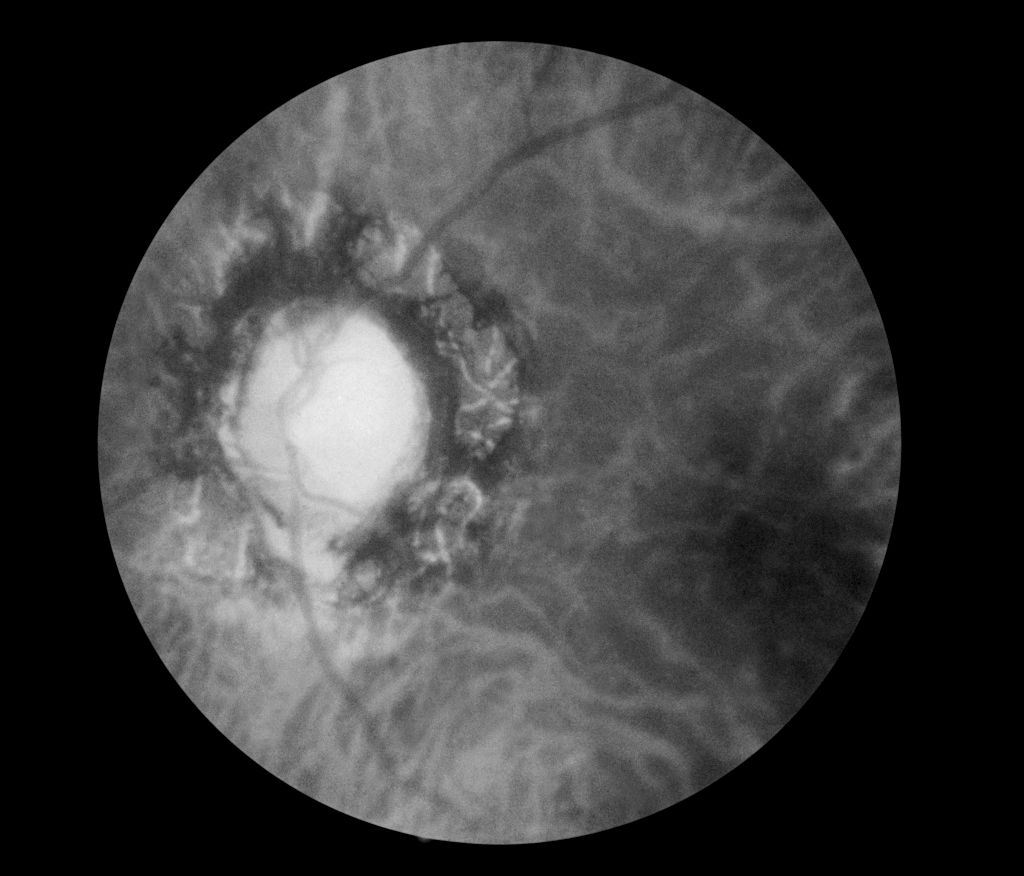

Patricia Bath wasn't just an amazing ophthalmologist; she was a global health advocate who transformed the eye care world. She grew up in Harlem, New York, and earned her medical degree from Howard University. She then trained at New York University, where she became the first Black resident in ophthalmology.